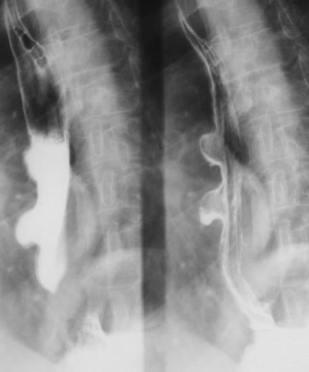

Neoplasm esofagian malign infiltrativ